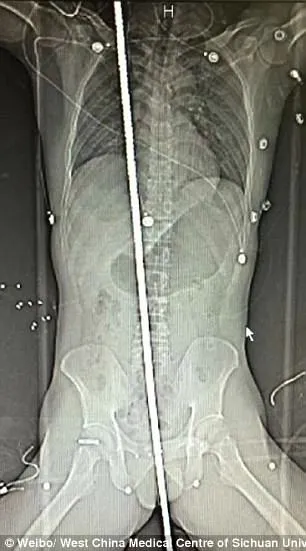

Hình chụp X-Quang bệnh nhân (trái) và thanh kim loại được lấy ra khỏi người nạn nhân sau ca phẫu thuật. Ảnh: Weibo

Theo phim chụp X-quang cho thấy, thanh sắt đã xuyên từ gần hậu môn nạn nhân, đi qua giữa bàng quang và ruột, mà không làm tổn thương bất cứ động mạnh chủ nào. Thanh sắt cũng xuyên nhẹ qua lá phổi phải rồi đi chệch qua tim. Nạn nhân cũng đã bị tràn khí phổi nhẹ nhưng đã được các bác sĩ phẫu thuật cắt bỏ một số tế bào tổn thương ở phổi và gan.